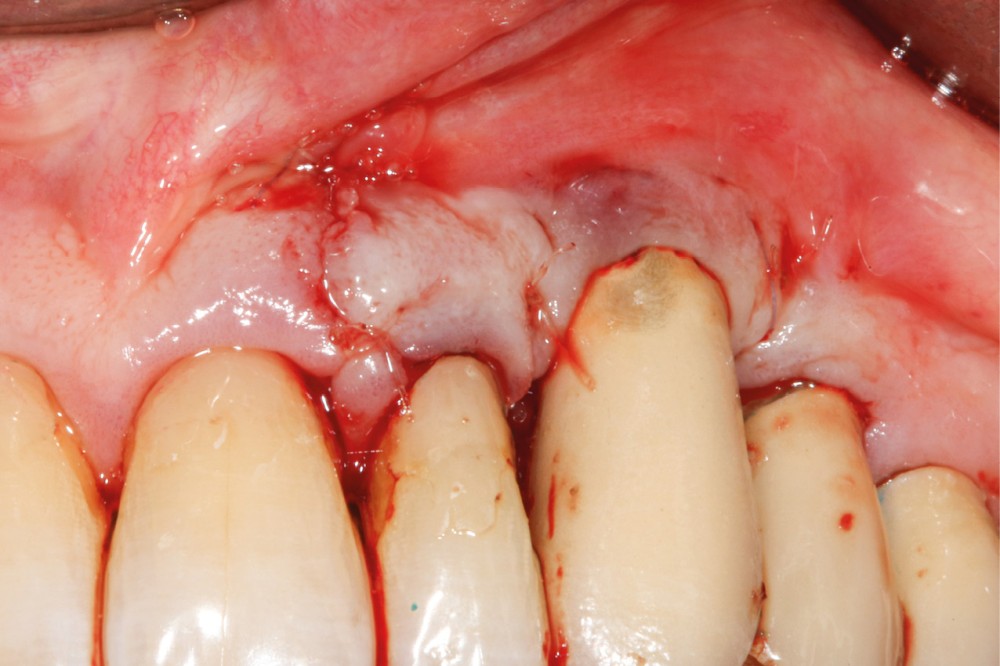

Le patient

- 70 ans

- Pas d’antécédents médicaux

- Ne fume pas

- Hygiène correcte

L’implant

- Site 23

- Mis en place il y a 12 ans